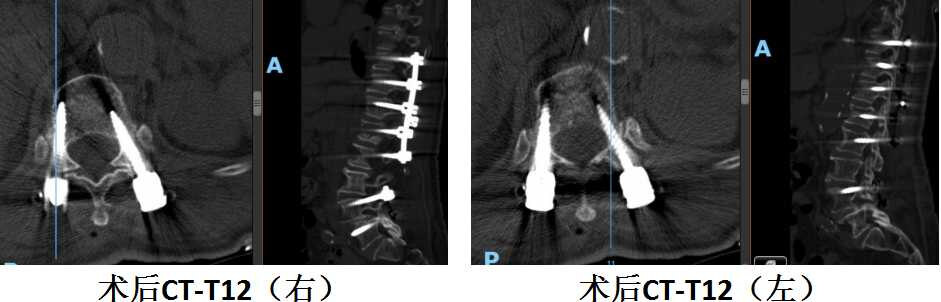

陈奶奶术后胸12水平螺钉位置良好